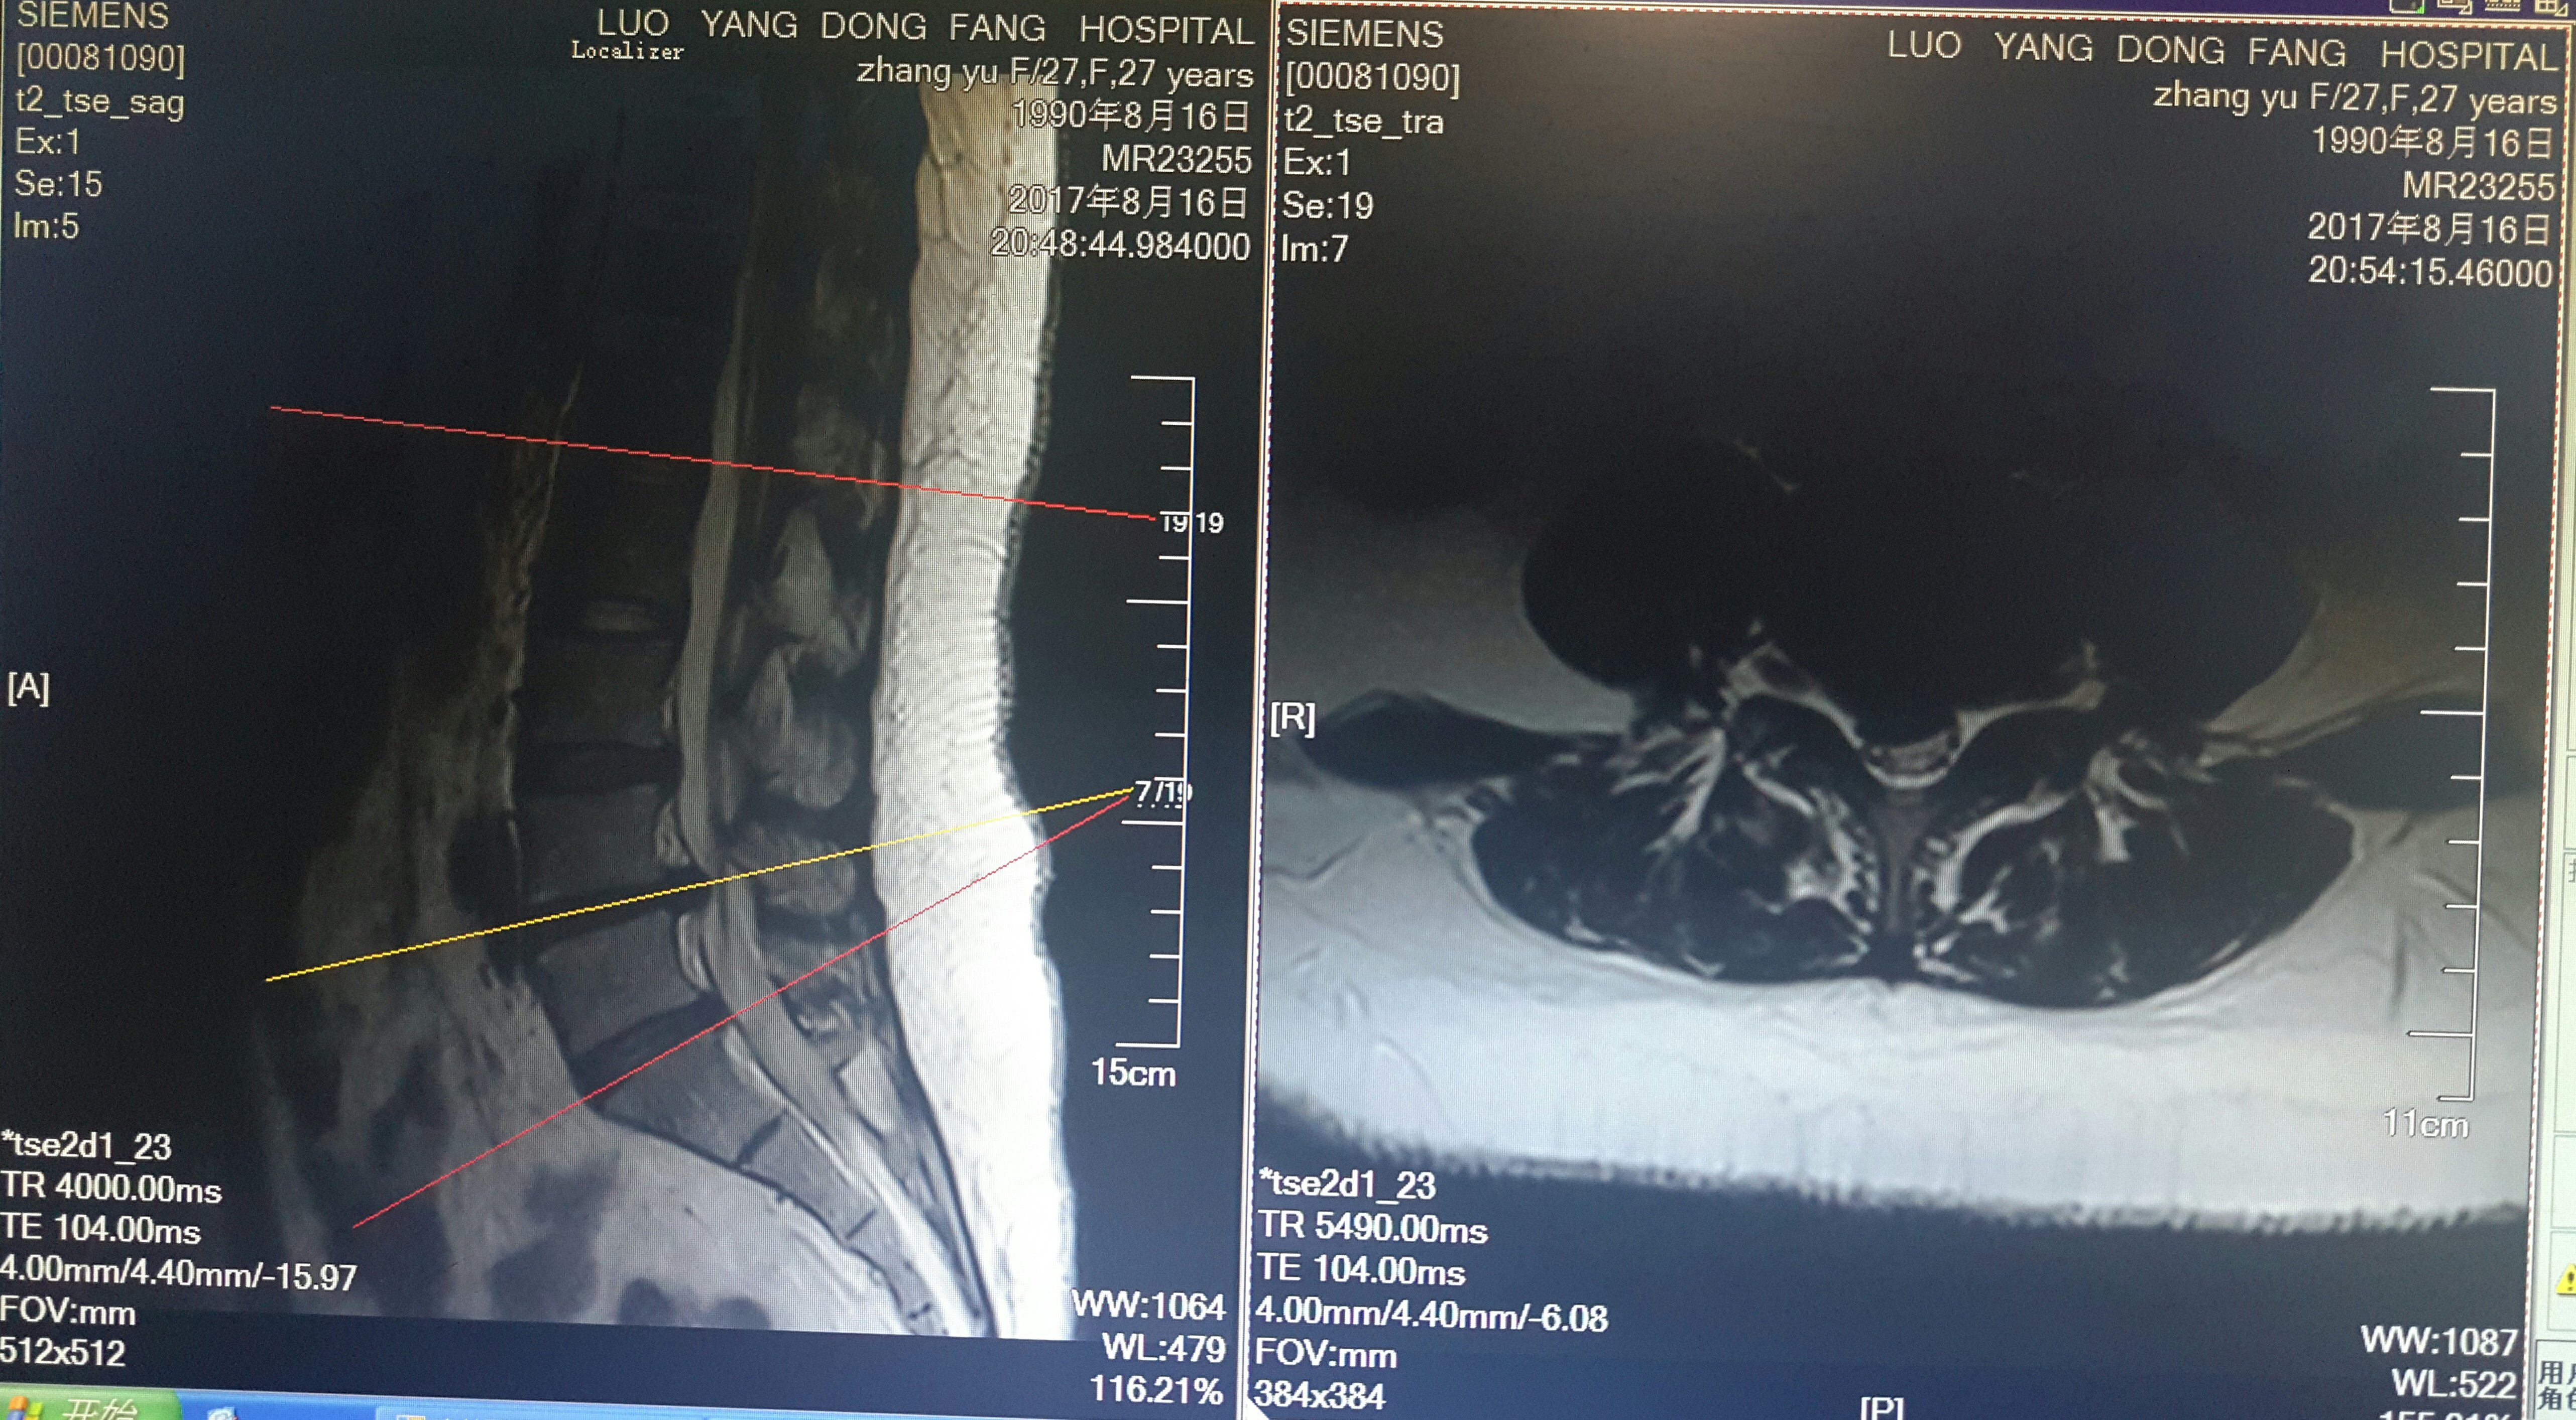

脊柱内镜翻修腰椎间盘突出症胶原酶溶核术后复

5310x2870 - 2720KB - JPEG